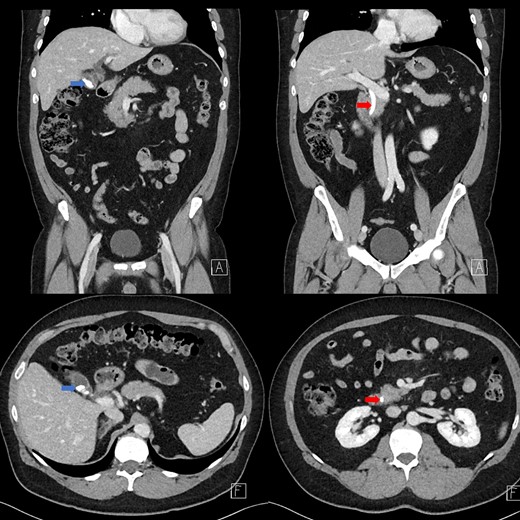

Portal venous contrast enhanced computed tomography (CT) of the abdomen revealed a layered dependent hyperattenuating material within the biliary tree (Fig. 1). The common bile duct (CBD) was dilated measuring 7.5 mm in diameter and filled along its course with radiodense material. Mild distention of the cystic duct and intrahepatic biliary tree were also noted with a 4 mm calculus in the CBD at the level of the duodenal ampulla (Fig. 2). There was no radiological evidence of cholecystitis.

Contrast-enhanced CT demonstrating limy bile within the gallbladder neck (left image) and CBD (right image).